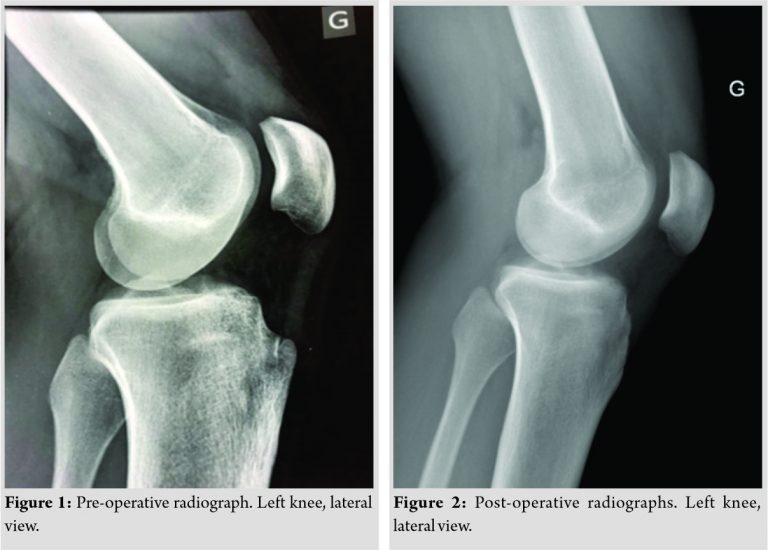

A 20-year-old patient initially presented with a long duration of anterior knee pain which was worse on kneeling, squatting, walking downhill, and also in sports participation (snowboarding). The patient underwent tibial tuberosity exostectomy through a midline incision at another institution and had excellent initial pain relief. Pre-operative radiographs (Fig. 1) demonstrated a prominent tibial tuberosity but no other pathology. Post-operative radiographs demonstrate the appearances after tibial tuberosity exostectomy (Fig. 2).